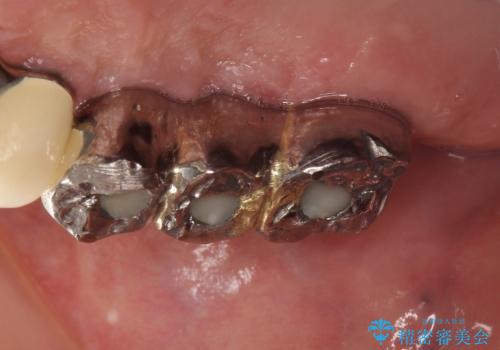

虫歯だらけ、歯周病 崩壊した口腔の再建 フルマウスリコンストラクション

かみ合わせの力が非常に強く、夜間の歯ぎしり・食いしばりもひどかったため、奥歯はメタルオクルーザルの設計でかぶせ物を製作しています。

かぶせ物の種類:PFZ / PFM metal occlusal